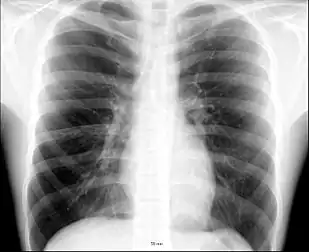

- (anatomy) The portion of the front of the human body from the base of the neck to the top of the abdomen; the thorax. Also the analogous area in other animals.

- She had a sudden pain in her chest.